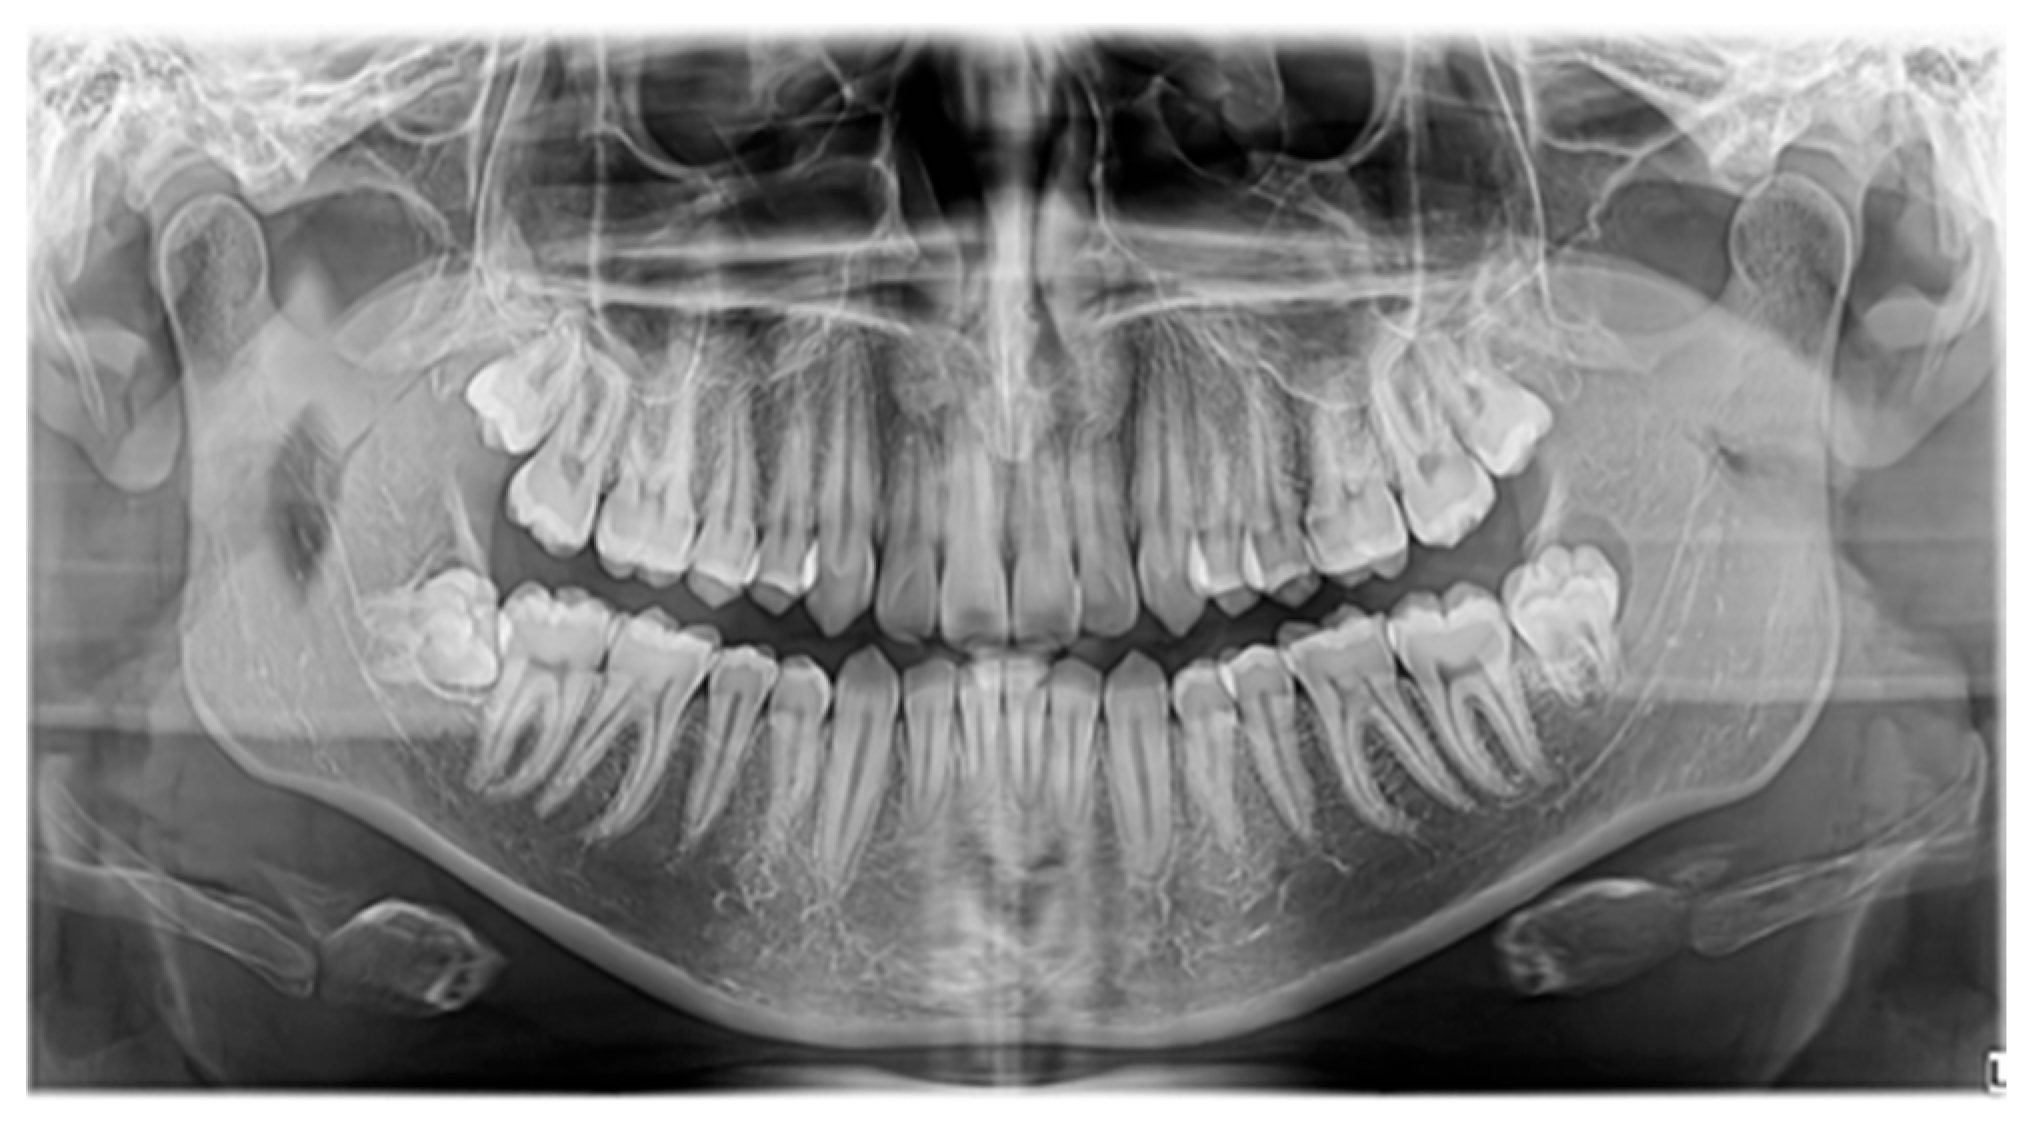

3.1. Case 1 (Figure 3, Figure 4 and Figure 5)